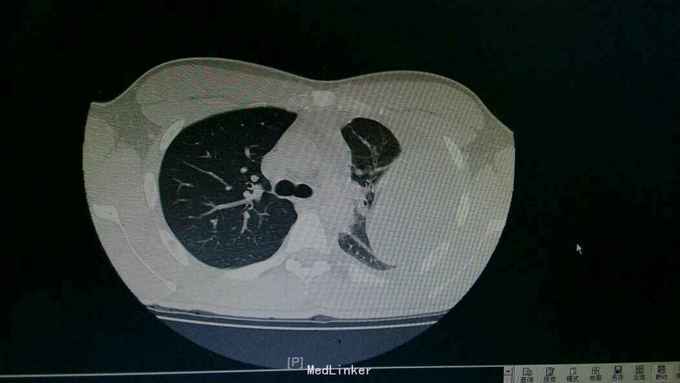

查体:神情,左侧呼吸运动减弱,叩诊浊音,左肺呼吸音低,右侧呼吸性正常。 辅查:胸部CT:左侧大量胸腔积液,左肺受压实变。复查胸片:左侧胸腔积液减前好转。胸水提示渗出性胸腔积液,淋巴细胞为主。T-SPOT:A:64个,B:42个。

诊断:结核性胸膜炎。 治疗:入院结合予以抗结核治疗,胸腔穿刺引流术。